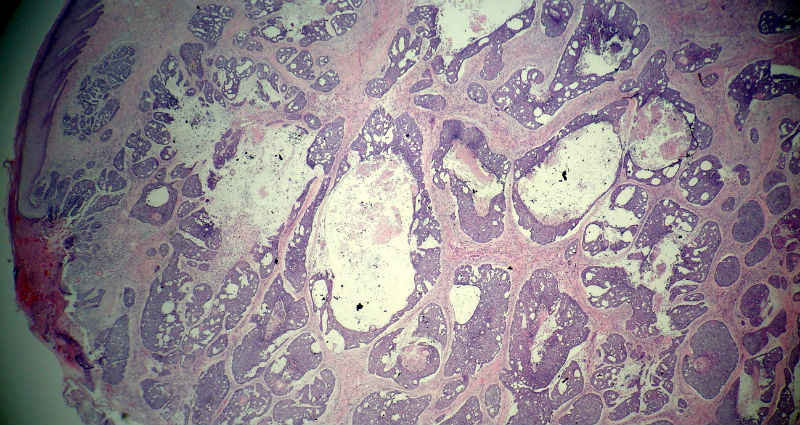

后枕部肿物

男,49岁,后枕部肿物3年,偶有破溃出血。

大体:皮肤半球形隆起,大小约2.3×2厘米,高出皮表0.8厘米,切面灰白,质地细腻。

似乎既有腺样结构,也有角化珠形成,还有细胞团内的粉刺样坏死。

有坏死、囊肿、钙化及胆固醇样裂隙等结构

考虑外毛根鞘肿瘤,局部癌变。

大部分区域看着象基底细胞癌,后面几张(11-14)看着象是鳞癌。综合考虑基底细胞样鳞癌。